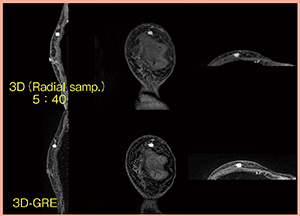

RVS用MRIは,コントラストが明瞭な画像を提供することが重要である。また,超音波診断装置では,MRIの画像はかなり拡大されて表示されるため,より高分解能画像の方がRVSの際には医師に貢献できると思われる。より高分解能なRVS用MRI画像取得のため,Radial sampling法を応用した3D-GREシーケンスを検討した。通常呼吸下でもモーションアーチファクトが大幅に低減された画像を取得することができるため,当院では腹部や骨盤部でも応用している。このシーケンスは,脂肪抑制は併用可能だが,パラレルイメージングを併用できないため撮像時間が長い(5min40s)が,ボクセルサイズはこれまでのシーケンスに比べて小さくすることができる。撮像条件・画像を示す(表3,図5)。Radial sampling法を応用した3D-GREシーケンスについては高評価をいただいている。現在,Radial sampling法で撮像する際には,造影剤は0.1mL/sで注入しているが,今後検討を加えていきたいと思っている。

図5 高分解能RVS用MRIの画像